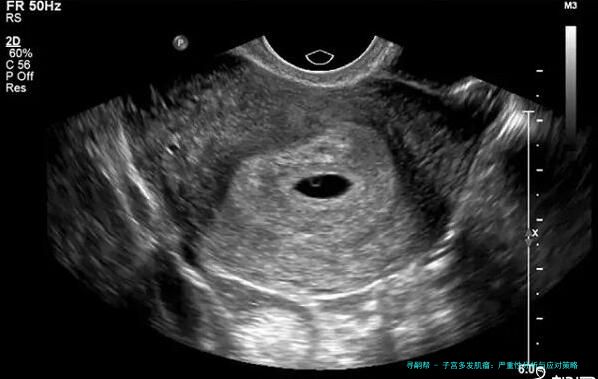

首先,子宫多发肌瘤简单来说,就是子宫里长了不止一个肌瘤。这些肌瘤是良性的肿瘤,由平滑肌和结缔组织组成,通常不会癌变。症状因人而异,有的人可能完全没感觉,而有的人则会经历月经量增多、腹痛、腰酸背痛,甚至影响排尿或生育。举个例子,我认识的一位阿姨,她就是因为月经期太长、量太大,才去医院检查,结果发现是多发肌瘤。医生说,这病在中年女性中更常见,但近年来年轻女性发病率也有上升趋势,可能跟生活压力大、饮食不规律有关。

说到严重性,这得看情况。从数据上看,大多数子宫多发肌瘤并不致命,属于可控的良性病变。根据近年医学研究,大约70%-80%的患者可以通过保守治疗或定期观察来管理,只有少数情况需要手术干预。比如,如果肌瘤大小超过5厘米,或者导致严重贫血、不孕等问题,那可能就比较棘手了。但别慌,我查了查资料,发现近年来微创手术技术进步很快,很多患者术后恢复得不错,生活质量也没受太大影响。不过,如果拖延不治,可能会加重症状,甚至引发并发症,比如贫血导致乏力、头晕,或者压迫膀胱引起尿频。所以,它不算绝症,但也不能掉以轻心。

治疗方面,选择挺多的。轻度的可以通过药物控制,比如用激素类药物调节月经;中重度的可能需要手术,比如子宫肌瘤剔除术或子宫切除术。近年来,微创技术如腹腔镜手术越来越普及,恢复快、创伤小。预防上,建议定期体检,尤其是B超检查,能早发现早处理。饮食上,多吃蔬菜水果,少吃红肉和高脂食物;运动也不能少,每周坚持散步或瑜伽,能帮助调节激素水平。我个人觉得,心态也很关键——别一听说肌瘤就恐慌,多和医生沟通,制定个性化方案,才是上策。